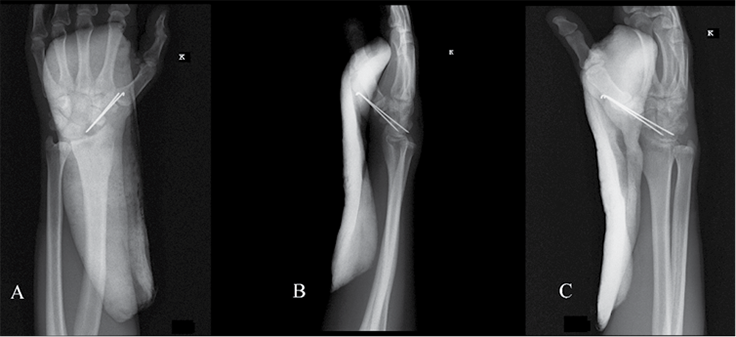

2 pav. Kairiojo riešo trijų krypčių rentgenogramos po operacijos: priekinė rentgenograma (A), šoninė rentgenograma (B), įstrižinė rentgenograma (C)

Operacijos metu atliktas pjūvis kairiosios plaštakos nugariniame paviršiuje tarp trečiojo ir ketvirtojo tiesiamųjų sausgyslių kompartmento laivelio projekcijoje. Naudojant bukąją ir aštriąją disekciją, pasluoksniui pasiektas kaulas. Rastas nesugijęs laivelio lūžis. Pašalintos proksimalinio laivelio segmento lūžgalių skeveldros, distalinė laivelio dalis rezekuota iki gyvų audinių. Vėliau atliktas apie 5 cm ilgio skersinis pjūvis ties VI dešiniojo šonkaulio krūtinkauliniu galu (mokslinėje literatūroje aprašoma atvejų, kai rekonstrukcijai naudojami V–IX šonkaulių osteochondriniai fragmentai [22, 24, 25]). Naudojant bukąją disekciją, pasluoksniui pasiektas ir nuo aplinkinių audinių, antkaulio ir krūtinplėvės atpreparuotas šonkaulis, atlikta dalinė jo rezekcija. Paimtas apie 3 cm kaulinės ir kremzlinės šonkaulio dalies fragmentas, kuris toliau formuotas pagal laivelio kaulinio defekto formą. Atsižvelgta į rekomendacijas, kad, formuojant transplantatą, jam fiksuoti ir funkcio­nuoti būtina palikti bent 2–3 mm storio šonkaulio kaulinio audinio ir 5 mm šonkaulio hialininės kremzlės [22, 24]. Autotransplantatas perkeltas į proksimalinį laivelio galą, fiksuotas dviem Kiršnerio vielų atkarpomis (žr. 2 pav.). Pjūviai pasluoksniui užsiūti, kairioji plaštaka imobilizuota gipso longete 3 mėn.

Pacientas pakartotinai klinikoje apsilankė praėjus 6 mėn. po rekonstrukcinės operacijos. Jis buvo patenkintas klinikiniais operacijos rezultatais, nes be apribojimų galėjo grįžti prie kasdienių veiklų ir darbo. Atlikus plaštakos goniometriją (žr. 3 pav.), įvertinti klinikiniai rezultatai, pasitelkiant modifikuotą Greeno ir O’Brieno riešo funkcijos balą ir Quick Disabilities of the Arm, Shoulder and Hand (QuickDASH) klausimyną, taip pat atliktos riešo rentgenogramos. Modifikuotas Greeno ir O’Brieno riešo funkcijos balas siekė 95. Balo įvertis, palyginti su pradiniu, prieš rekonstrukcinę operaciją apskaičiuotu įverčiu, padidėjo daugiau negu 20 balų, visų vertintų kategorijų, išskyrus riešo judesių amplitudę, įvertinimai buvo aukščiausi, atitinkantys sveikosios plaštakos rodiklius. Įvertinus Quick Disabilities of the Arm, Shoulder and Hand (QuickDASH) klausimyną, apskaičiuota skaitinė išraiška siekė 4,55 balų, t. y., palyginti su pradiniu įverčiu, sumažėjo 9,09 balų. Paciento atsakymuose fiksuoti minimalūs kasdienės veiklos ribojimai. Taip pat atliktos kairiojo riešo trijų krypčių rentgenogramos (žr. 4 pav.).

4 pav. Kairiojo riešo trijų krypčių rentgenogramos, praėjus 6 mėn. po operacijos: priekinė rentgenograma (A), šoninė rentgenograma (B), įstrižinė rentgenograma (C)